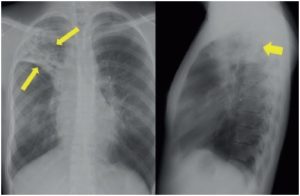

В последствии они трансформируются в отложения солей кальция, которые никак себя не проявляют и диагностируются случайно при прохождении флюорографии или рентгенологического исследования. Как выглядят кальцинаты на рентгеновском снимке показано на фото ниже.

Кальцинаты в легких на рентгене

Сами по себе эти образования не опасны и никак не нарушают функции легких. Однако кальцинаты способствуют снижению местных защитных сил и общей резистентности, поэтому люди с такой патологией более подвержены бронхо-легочным инфекциям. Им рекомендуется регулярно проходить профилактические осмотры и дважды в год делать флюорографию.